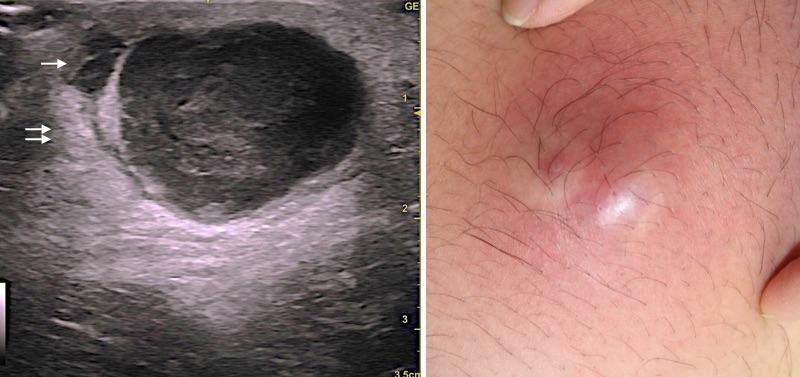

今回の症例も頚部の粉瘤腫で、くりぬき法を行います。

いつものように、くり抜き法で20分以内に終了するぞ!と思いきや、今回はやや慎重にならざるおえません

なぜなら恐怖のErb's pointが近くにあるからです

腫瘍の袋も絞り出されました。できるだけまわりの組織に触れないように袋を取り出します。慎重に!